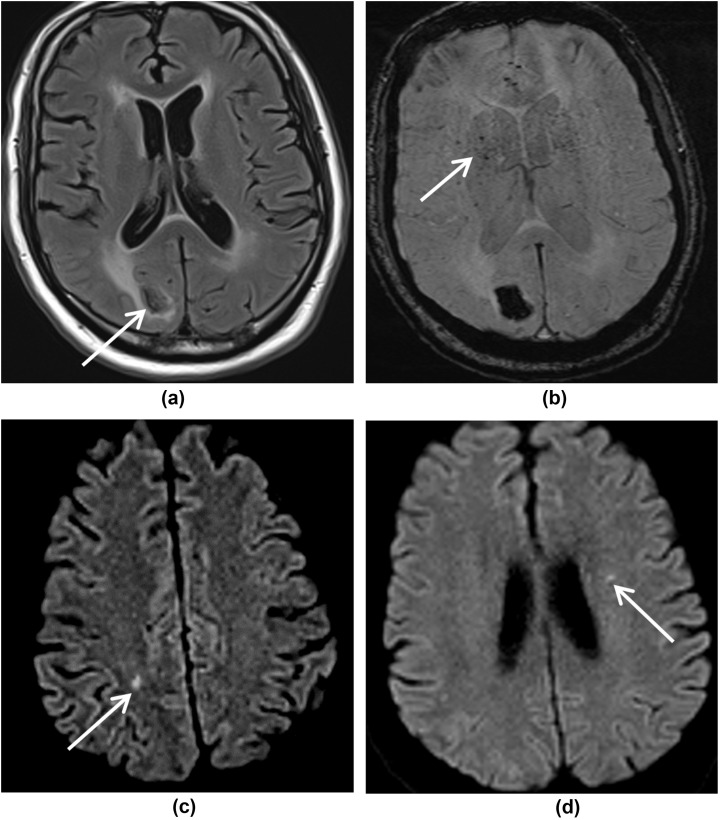

Figure 5.

MRI images showing symmetrical white matter signal change. (a) T2W, (b) FLAIR, (c) DWI, and (d) ADC images show white matter hyperintensities in the deep watershed territory bilaterally in the posterior frontal lobes, giving an ADEM-like appearance. (e) SWI image shows small foci of blooming within these lesions indicating microhaemorrhages. In addition, there are subcortical white matter changes in the left occipital lobe with parenchymal haemorrhage on (f) T2W, (g) FLAIR, and (h) SWI images.

Hypoxic–ischaemic changes were seen in one patient who had a cardiac arrest. MRI showed bilateral hypoxic–ischaemic changes with restricted diffusion in the basal ganglia, tail of hippocampi and cerebral peduncles (Fig 6 ). There were also necrotic changes seen in the nigrostriatal tract. Dentate nuclei and thalami were also involved, showing high signal on T2/FLAIR. Microhaemorrhages were seen in the splenium of corpus callosum. This patient had two MRI studies within an interval of 6 days; the first study demonstrated restricted diffusion in the tail of hippocampi and thalami. Second MRI showed more marked changes in the basal ganglia including the nigrostriatal tract. Pseudonormalisation of ADC was noticed in the thalami on this second study, reflecting evolving ischaemic changes.

Figure 6.

MRI images showing bilateral hypoxic–ischaemic changes. (a,b) DWI and ADC images show high diffusion signal with corresponding low ADC in the basal ganglia (thin arrow), tail of hippocampi (bold arrow), and (c) cerebral peduncles. (d) FLAIR image demonstrates high signal in the thalami and (e) dentate nuclei. (f) SWI shows microhaemorrhages in the splenium of the corpus callosum.

ADEM-like changes were seen in one patient who was slow to regain consciousness and had a background of diabetes and hypertension. MRI demonstrated bilateral symmetrical white matter hyperintensities with microhaemorrhages in the posterior frontal lobes (Fig 5). Subcortical white matter changes were also present in the left occipital lobe with parenchymal haemorrhage.